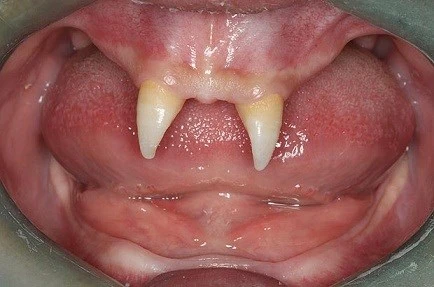

Cậu bé 16 tuổi chỉ mọc 2 răng nanh: Đó là một cậu bé 16 tuổi người Trung Quốc. Cậu bé này chỉ mọc 2 cái răng trước sắc và nhọn trông như răng của ma cà rồng chuyên hút máu người trong truyền thuyết.

Theo lời các bác sỹ, cậu bé Trương Thành mắc một bệnh lạ nghiêm trọng và hiếm gặp và thường gặp phải ở nam giới. Người mắc chứng bệnh này sẽ ít toát mồ hôi và lông mọc ít hơn người bình thường.